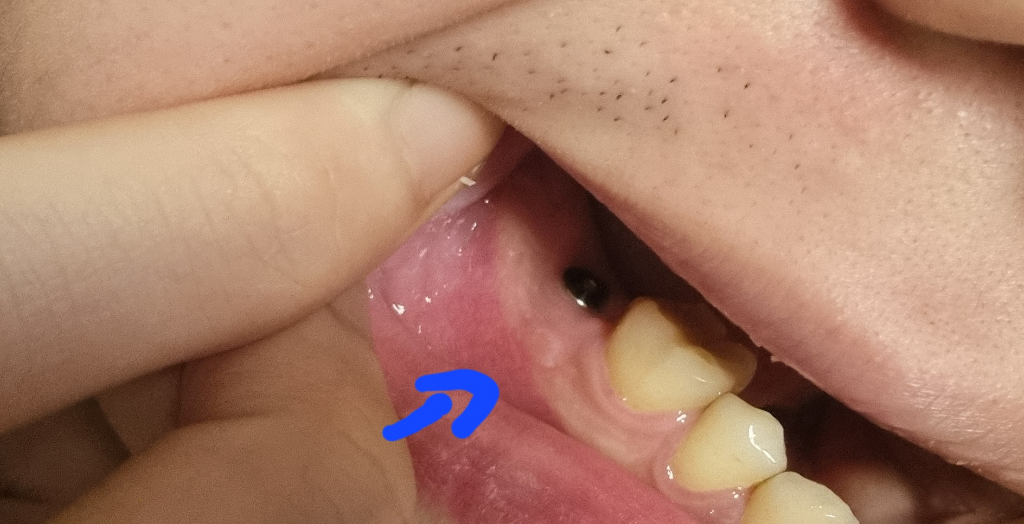

혹시 임플란트 염증 인가요 ㅠㅠ 급합니다 ㅠㅠ

1월달 중반에 발치후 즉시 식립 임플란트를했는데요 ㅠㅠ 어제 보니까 임플란트 심은곳 어금니쪽이 잇몸을 살짝 건드리면 피가나서 헐은줄알고 연고를바르고잤는데 오늘이러네요 ㅠㅠ 식립했던 병원이 사정상 이번주 휴무인지라 다음주월요일에 방문이 가능한데 어떡하나요ㅠㅠ 저쪽 부은쪽에잇몸건드리면따갑기는합니다 ㅏ

사진으로 봤을 경우에는 잇몸의 염증이 있는 것으로 보이진 않습니다. 임플란트를 한 부위는 자극을 하지 않는 것이 좋기 때문에 무리에서 확인을 하거나 하지 않는 것이 좋습니다. 자세한 확인을 위해서 치과에서 진료를 받아보는 것을 권유드립니다.

잇몸염증은 아니고 저부위가 자극을 받아서 구내염이 생긴거 같습니다. 큰 문제가 잇는건 아니니 너무 걱정하지 않으셔도 될것같습니다.

사진상 그리고 증상으로 봤을 때 잇몸에 염증이 있는 것 같습니다. 해당 부위 잇몸 염증과 관련해서 치과를 가서 검진을 받아보시고 필요하다면 잇몸치료를 하시면 좋을 것 같습니다.

우선 소염진통제 복용이 염증 및 통증경감에 도움이 되기에 복용을 하며 지켜보고 ,가능한 해당부위에 자극이 가지 않도록 하길 권합니다.